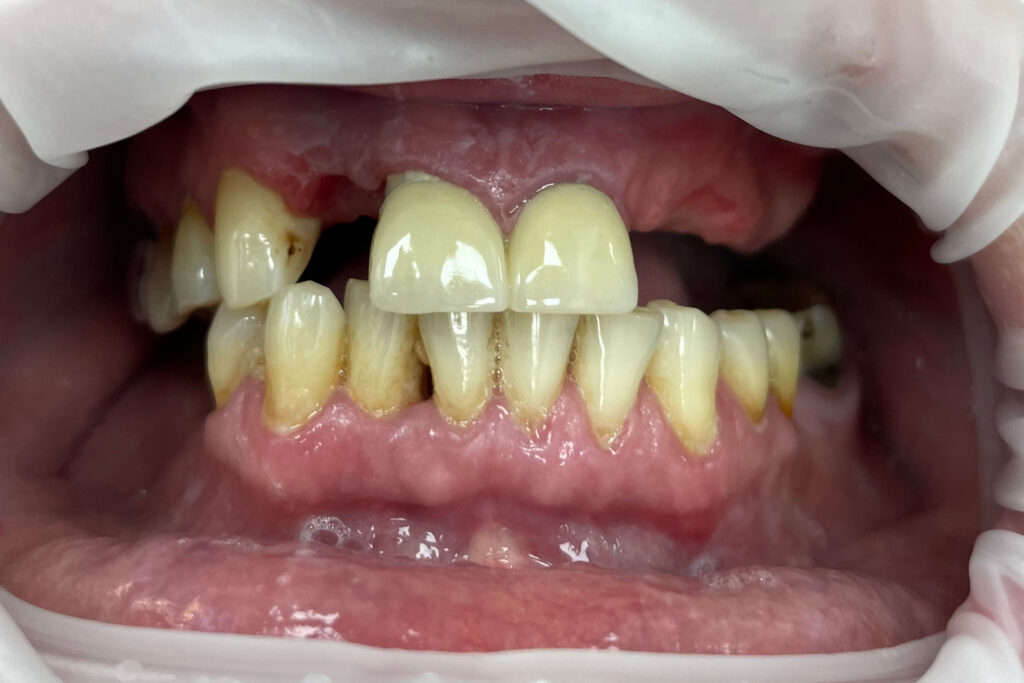

Ситуация до лечения

Жалобы: Пациент обратился к нам с целью проведения комплексной имплантации верхней челюсти.

Диагноз: Частичная вторичная адентия верхней челюсти.

пациент до протезирования

После консультации было принято решение об удалении зубов на верхней челюсти, которые находились в неудовлетворительном состоянии

и проведении комплексной имплантации по системе All-on-4.